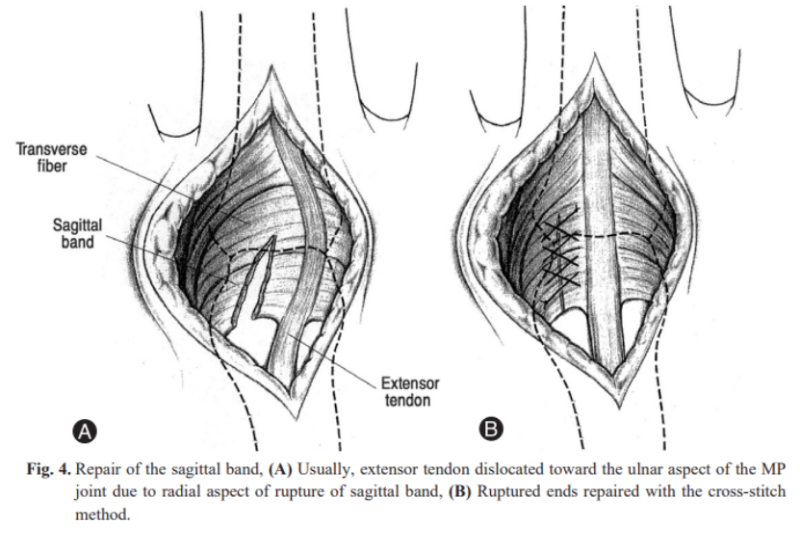

따라서 시상대가 찢어지게 되면 아래 그림처럼 손가락폄근힘줄이 제자리에서 이탈돼서 옆으로 빠지게 됩니다.

1. 직접 봉합(Direct repair)

직접 꿰맬 수 있는 경우에 시행합니다.